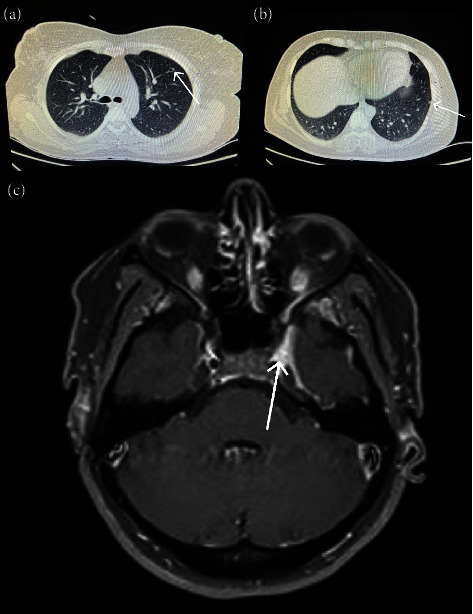

Background: Tolosa-Hunt syndrome (THS) is a rare disorder involving the orbital and retro-orbital space. The typical symptoms include sensory loss in the trigeminal nerve's distribution, orbital pain, swelling, headaches, and cranial nerve palsies. Case Presentation. We report a 40-year-old female who initially presented with biparietal headache, unresponsive to medication, which then led to ophthalmoplegia and orbital pain. Serological findings demonstrated positive CANCA-PR3. She was initially treated with 1 g pulse methylprednisolone for three days. Based on the rheumatological evaluation and her positive lung nodule, hematuria, dysmorphic red blood cells, and positive antiproteinase 3 classic antineutrophil cytoplasm antibodies (CANCA-PR3) and also based on the diagnostic criteria for granulomatosis with polyangiitis criteria for Wegner disease, her treatment was continued with prednisolone 1 mg/kg and also rituximab at the first and 14th day of treatment.

Conclusion: In our case of THS, we achieved satisfactory improvement in symptoms through the administration of high-dose steroids.